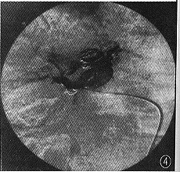

图4 栓塞后肝动脉DSA示畸形血管影消失,未见肝中静脉提前显影

介入治疗:采用Seldinger技术经右股动脉置入肝动脉导管于病变动脉的近端,先后共释放10枚Cook公司生产的MWCE 38-8-5型不锈钢圈。肝动脉造影显示HHT的供血动脉及迂曲扩张的毛细血管影完全消失,肝中静脉显影正常(图4)。患者术后腹痛消失,3 d后康复出院。